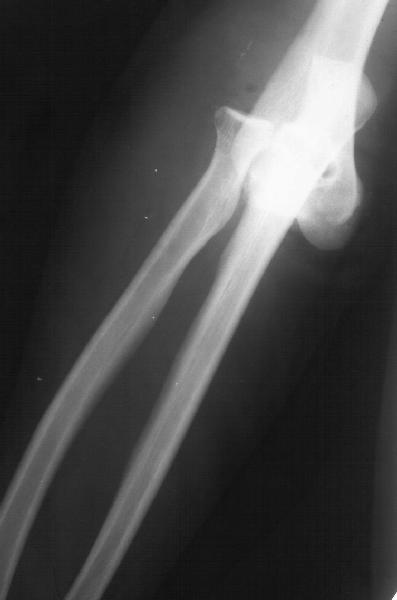

Пациентка 48 лет при падении с 5 этажа получила травму 28.04.02. Среди прочих повреждений был открытый задний вывих предплечья (см. снимок). Он был сразу вправлен, рана 6 см по внутренней поверхности

области локтевого сустава была обработана по месту первичного поступления. К нам поступила 7.05.02. Рана зажила первичным натяжением. Вчера, то есть через три недели после вправления, сняли повязку для разработки движений. Выявлено, что предплечье легко смещается медиально, и вправляется. Движения в локтевом суставе пока плохие. Свежие снимки и в правильном положении, и в подвывихе прилагаются. Вопрос - что делать? Продлить иммобилизацию гипсом? Идти на ревизию и восстановление внутренней боковой связки? Наложить шарнирный аппарат? Заранее спасибо. -- Best regards, Alexander N. Chelnokov